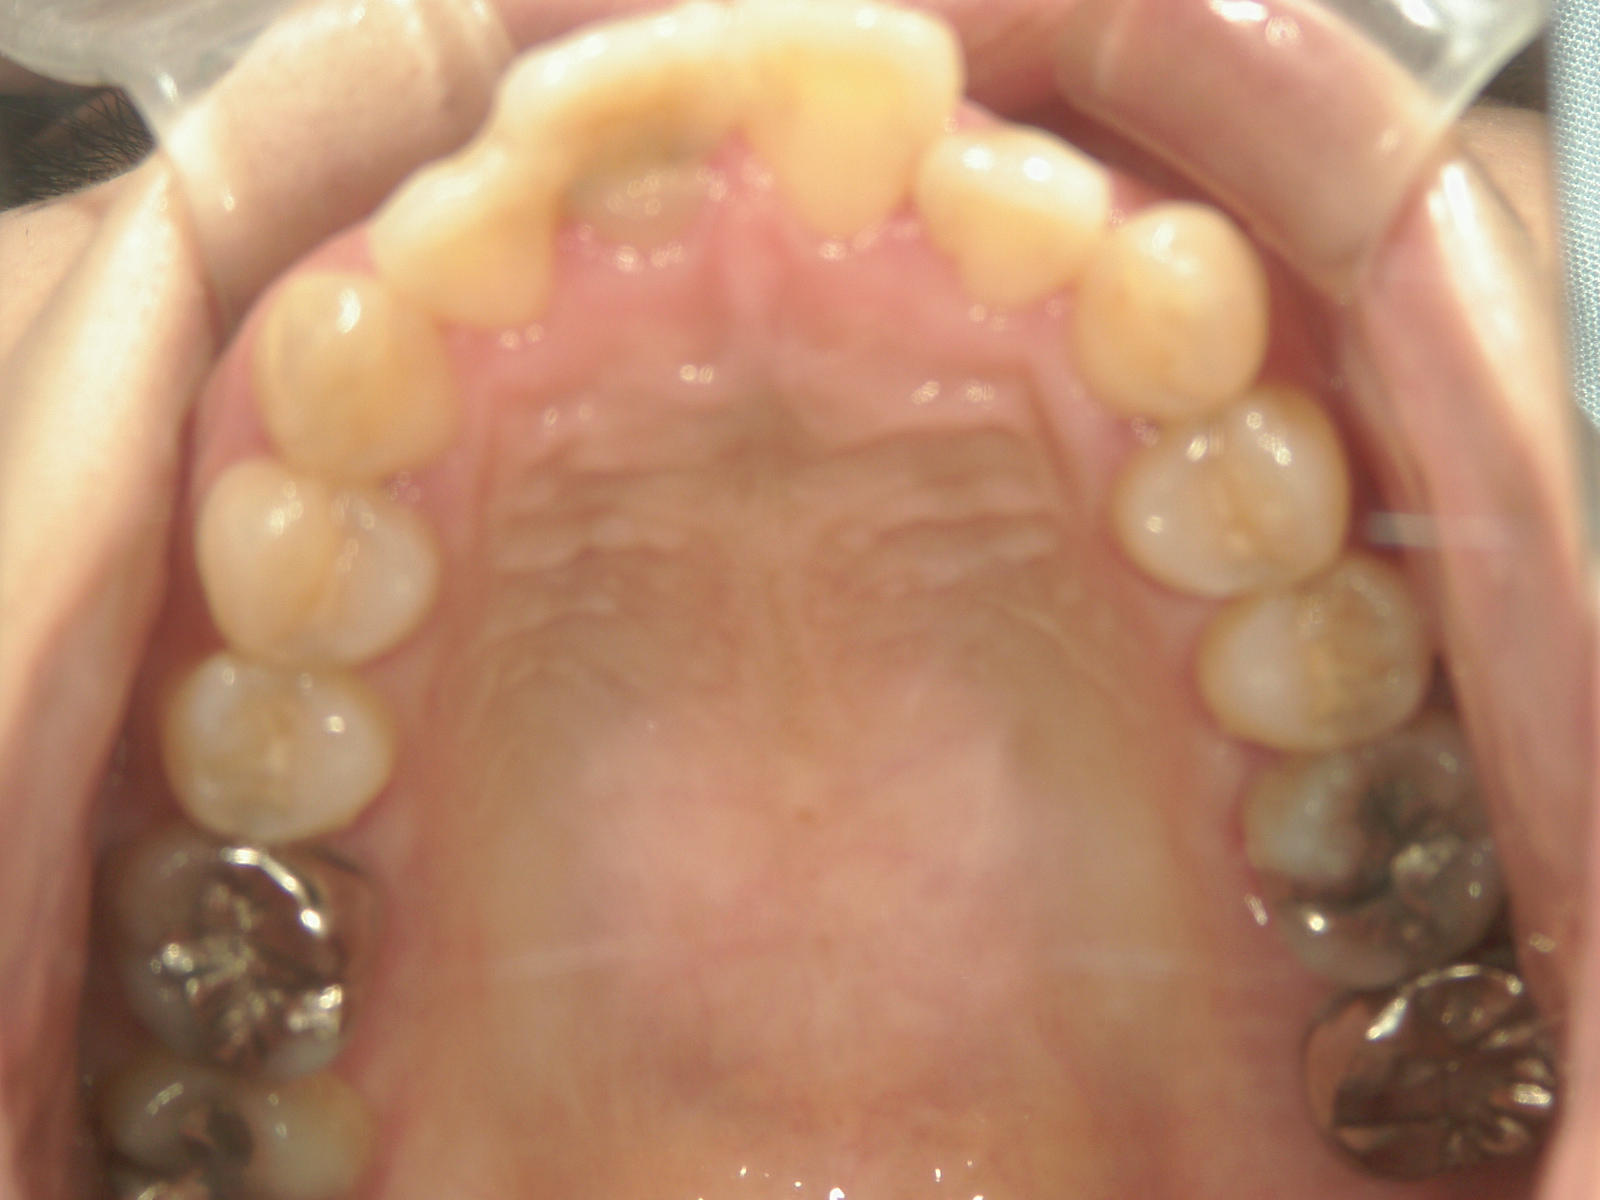

全顎ワイヤー矯正 症例(70)

主訴: 8年前の事故でぶつけて歯根吸収していた為、前突・叢生が気になる。

右上中切歯 抜歯後、空隙を閉鎖しました。

左右下 第一小臼歯2本、左上 第一大臼歯1本、右上 前歯1本を抜歯。